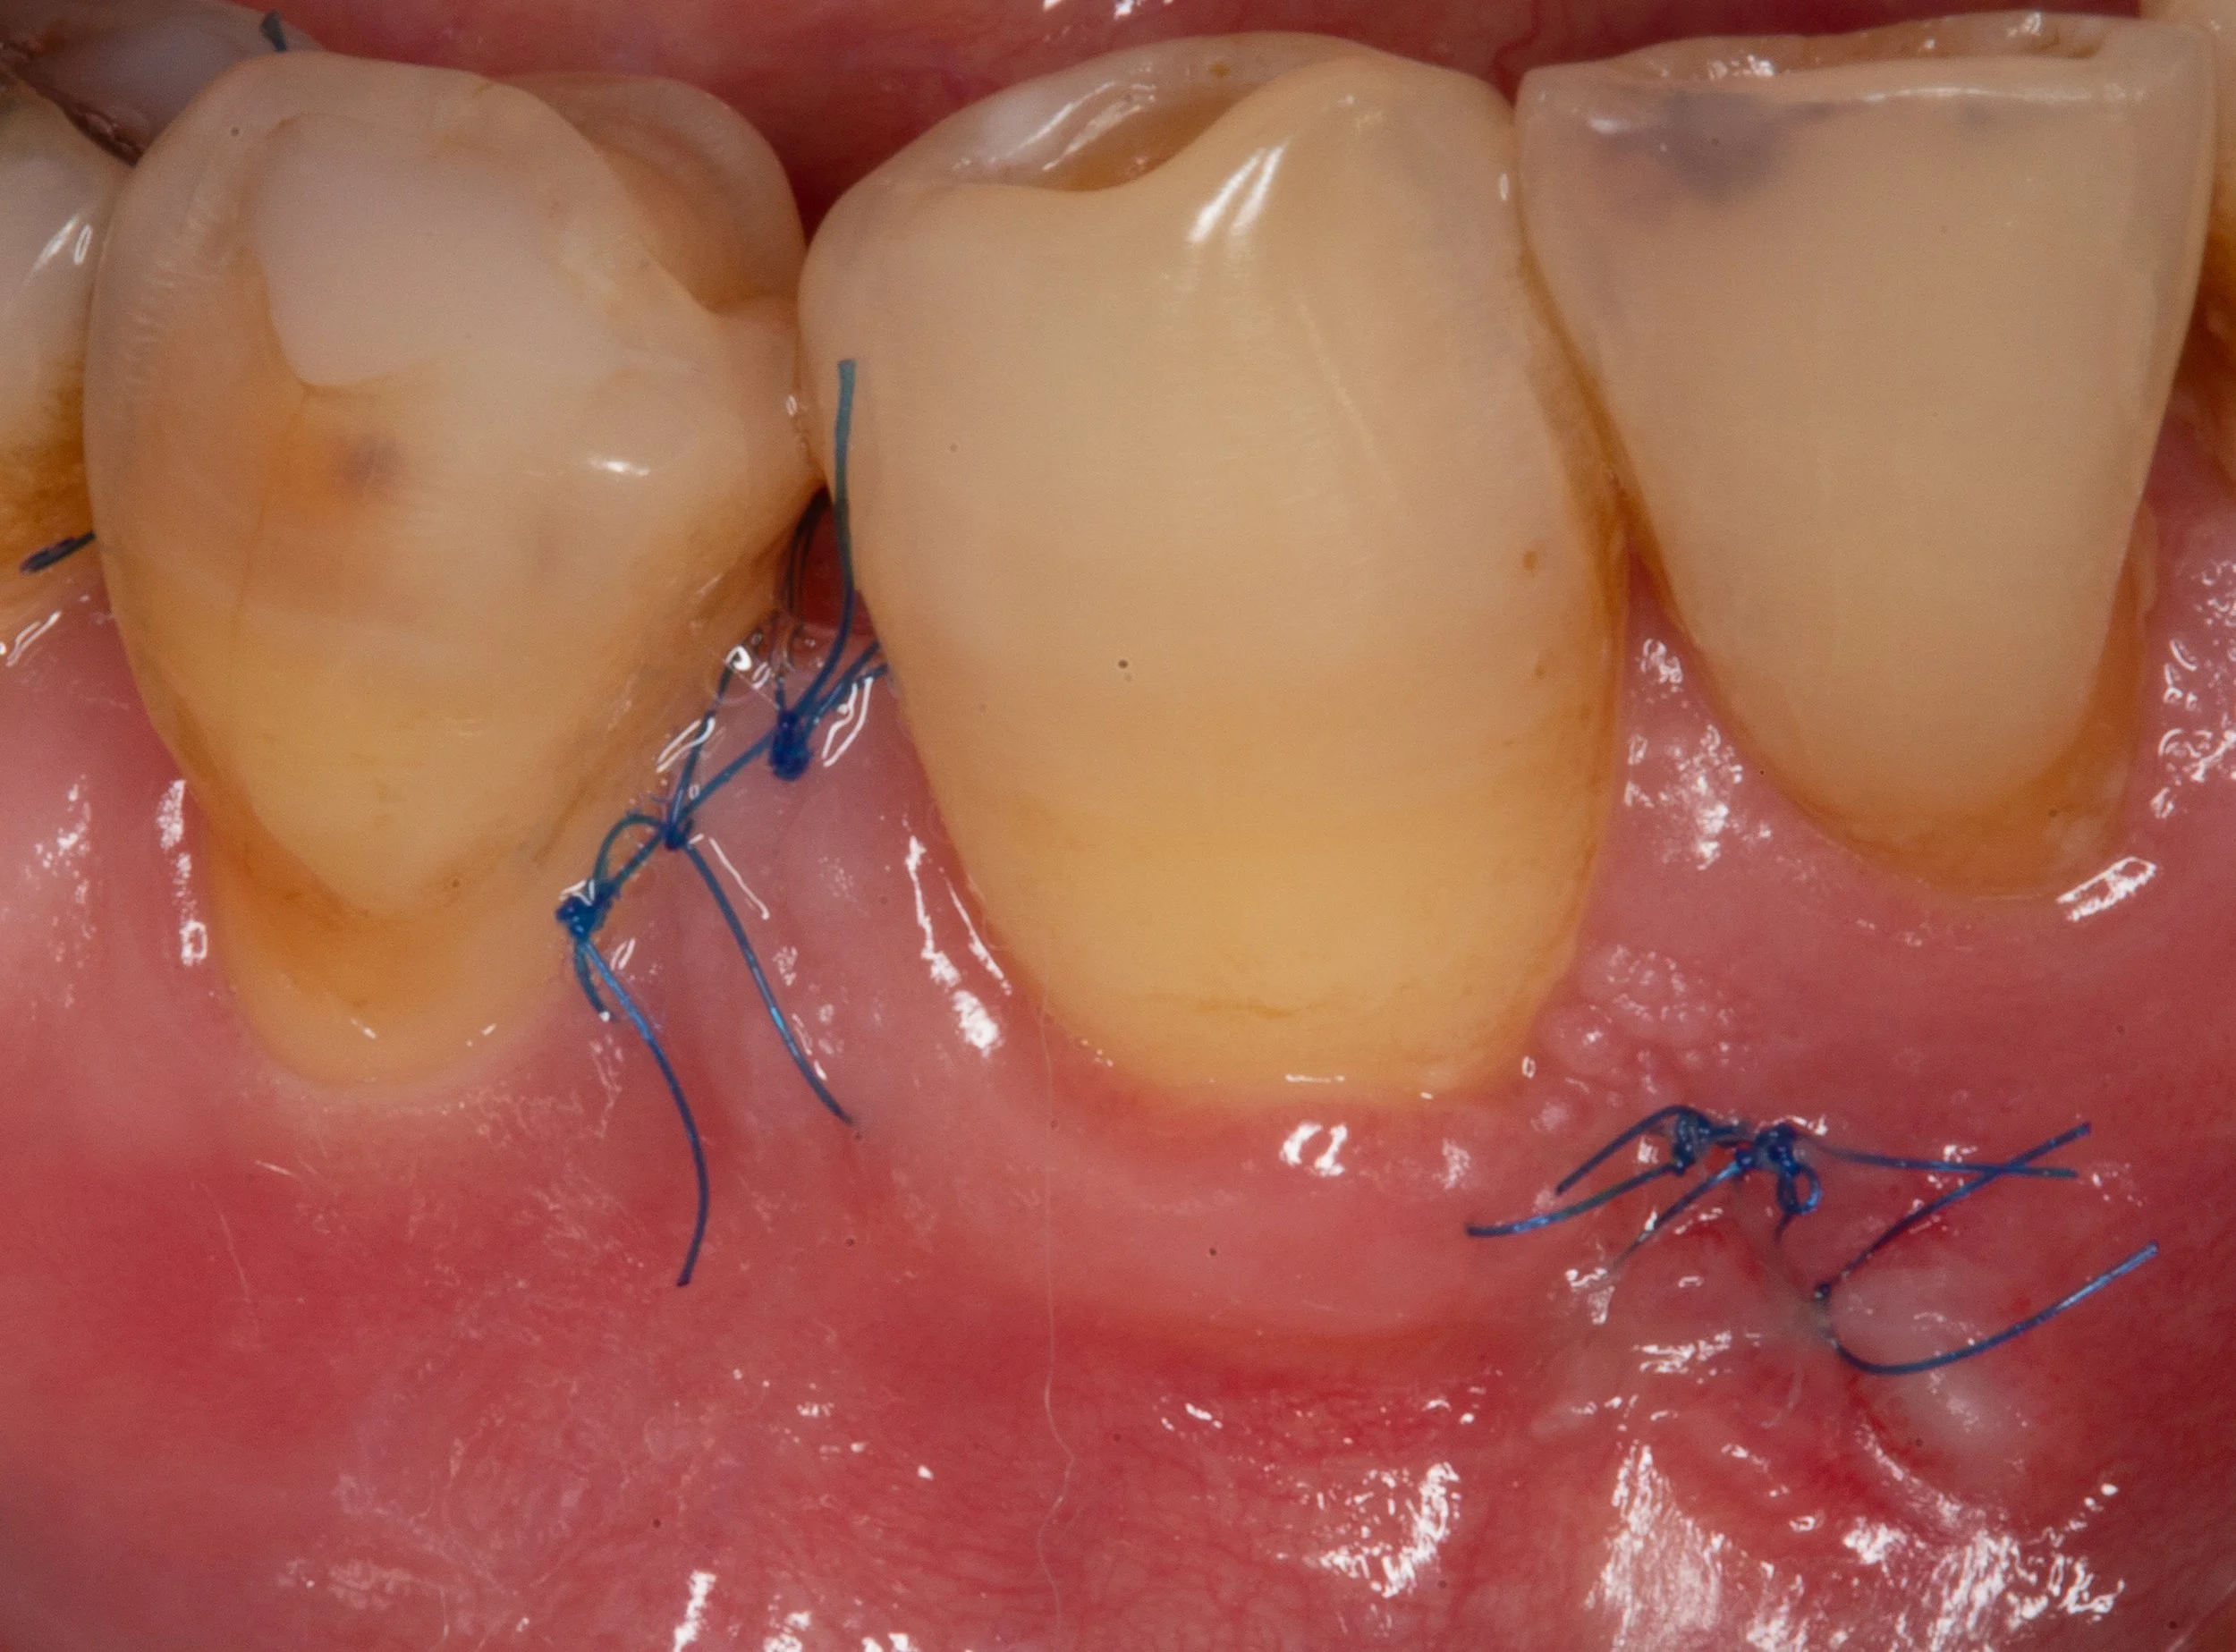

Periodontal disease will cause more bone loss until the bacteria have been removed. In this scenario, a bone graft was obtained from a tissue bank and used to rebuild the lost bone and tooth support.

The treatment of periodontal disease is generally performed under local anesthesia in an outpatient setting. Initial healing can be expected in 2-weeks with minimal discomfort and interruption to your daily activities. Complete healing and return to regular, frequent cleanings is expected after 3-4 months.

Periodontal gum disease healing after surgery